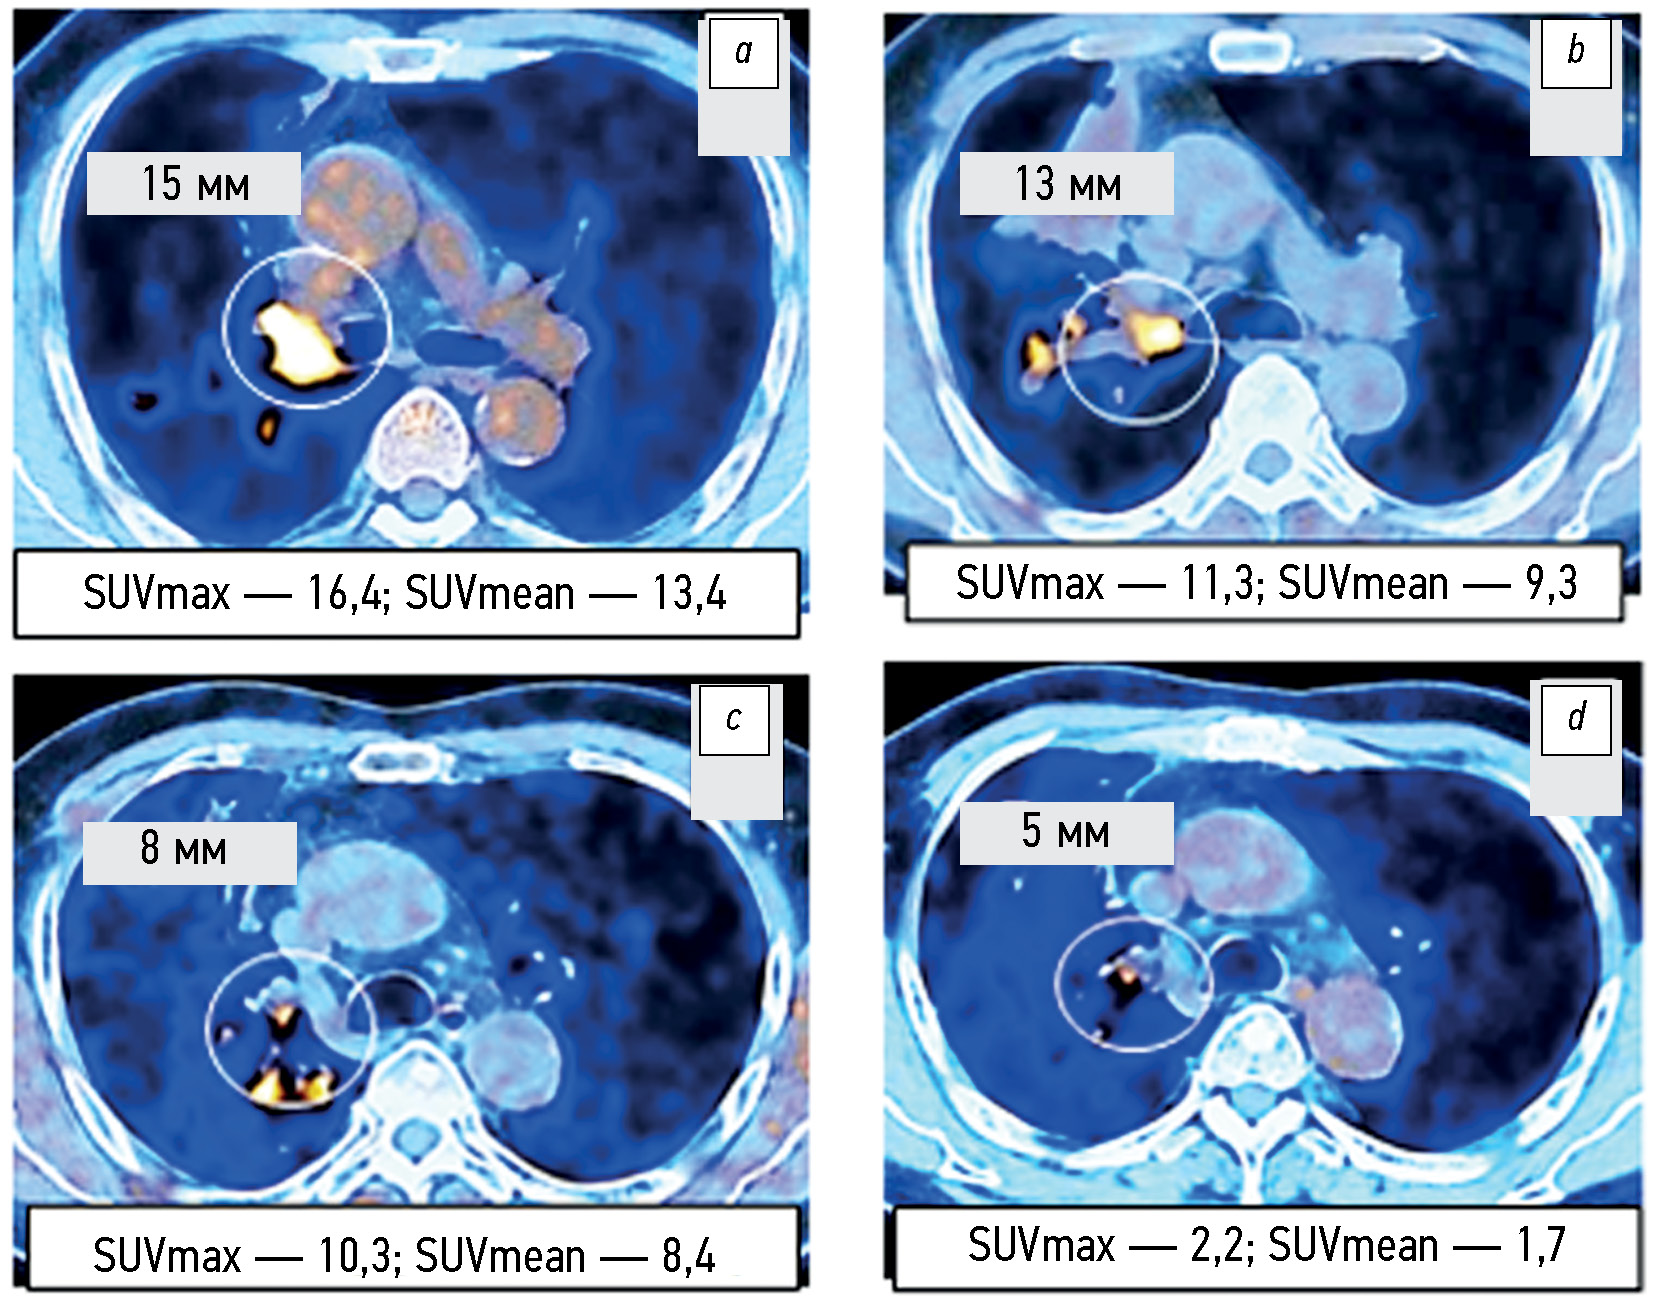

AIM: To explore the capabilities of positron emission tomography combined with computed tomography based on the RECIST 1.1 criteria and changes in SUVmax and SUVmean metabolic parameters for the comparative assessment of the tumor response to targeted monotherapy and combination therapy with tyrosine kinase inhibitors in patients with EGFR-mutant non-small cell lung cancer.

MATERIALS AND METHODS: The 2019–2022 examination records of positron emission tomography combined with computed tomography with 18F-fluorodeoxyglucose (18F-FDG) in 105 patients with non-small cell lung cancer were analyzed, including 75 patients with EGFR-activating mutation. The radiation exposure was adjusted individually and ranged from 45 to 90 mSv. The volume activity of the 18F-FDG radiopharmaceutical was 260–500 MBq. The change in the total largest diameters of the target lesions and SUVmax and SUVmean metabolic parameters were assessed before treatment initiation and 1.5–2.0 months after it. The follow-up duration for the changes in positron emission tomography combined with computed tomography findings in 17 patients with non-small cell lung cancer was at least 12 months.

RESULTS: According to positron emission tomography combined with computed tomography images and SUVmax and SUVmean changes, disease progression was significantly less common (p = 0.043 and p =0.029) in patients with EGFR-mutant non-small cell lung cancer from Groups 2 and 3 who received combination therapy with tyrosine kinase inhibitors and bevacizumab or chemotherapy than in Group 1 and control group (4.2% vs. 20.0%–21.8%). An insignificant trend (p =0.092) to a higher partial response to therapy (58.3% vs. 40.0%) was noted. Similar changes in the total largest diameters of the target lesions at the early stage of therapy appeared to be not significant (p =0.187). Within the long-term follow-up of some patients with non-small cell lung cancer, in at least 50% of cases, changes in the total largest lesion diameters are consistent with the relevant SUVmax and SUVmean alterations found in the first control study.

CONCLUSIONS: Based on the positron emission tomography combined with computed tomography data and alterations in SUVmax and SUVmean metabolic parameters, the early tumor response to combined therapy with tyrosine kinase inhibitors and bevacizumab or chemotherapy compared with targeted monotherapy with tyrosine kinase inhibitors or chemotherapy of the control group was characterized by a significantly lower rate of metabolic disease progression, although a similar tendency of the change in the total largest diameters of target lesions according to RECIST 1.1. was not significant. Changes in SUVmax and SUVmean metabolic parameters at the early stage of therapy are at least 50% faster than similar changes in the total largest diameters of the target lesions, which can be used for the timely identification of patients with a high risk of further progression as determined by RECIST 1.1.